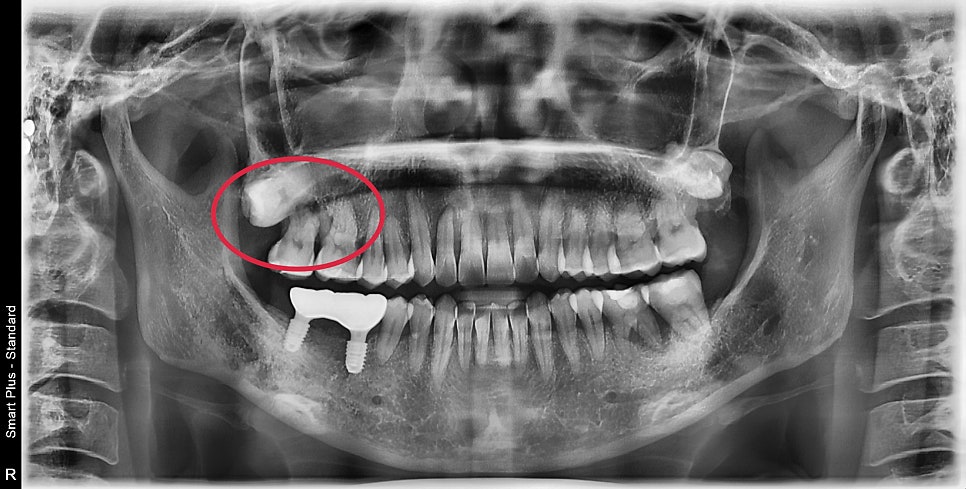

엑스레이상에서 뿌리 주변 염증소견이 보여 확실히 확인하기 위해

3D CT촬영을 한 후 설명을 드렸습니다.

해당 부위의 여러 단면을 촬영한 3D CT입니다.

화살표 표시된 부분이 하얗게 뼈로 채워져있어야 할 공간이

염증에 의해 뿌리 주변이 모두 녹아 뿌리가 외부 자극에 그대로 노출이 되어있었습니다.

이미 뿌리 밑단까지 녹아있었기에 해당 치아와 그 옆의 사랑니까지 발치가 필요해 보였습니다.

또한, 그 옆의 치아도 염증이 퍼져 치주 질환에 이환되어 뿌리의 절반이 노출되었습니다.